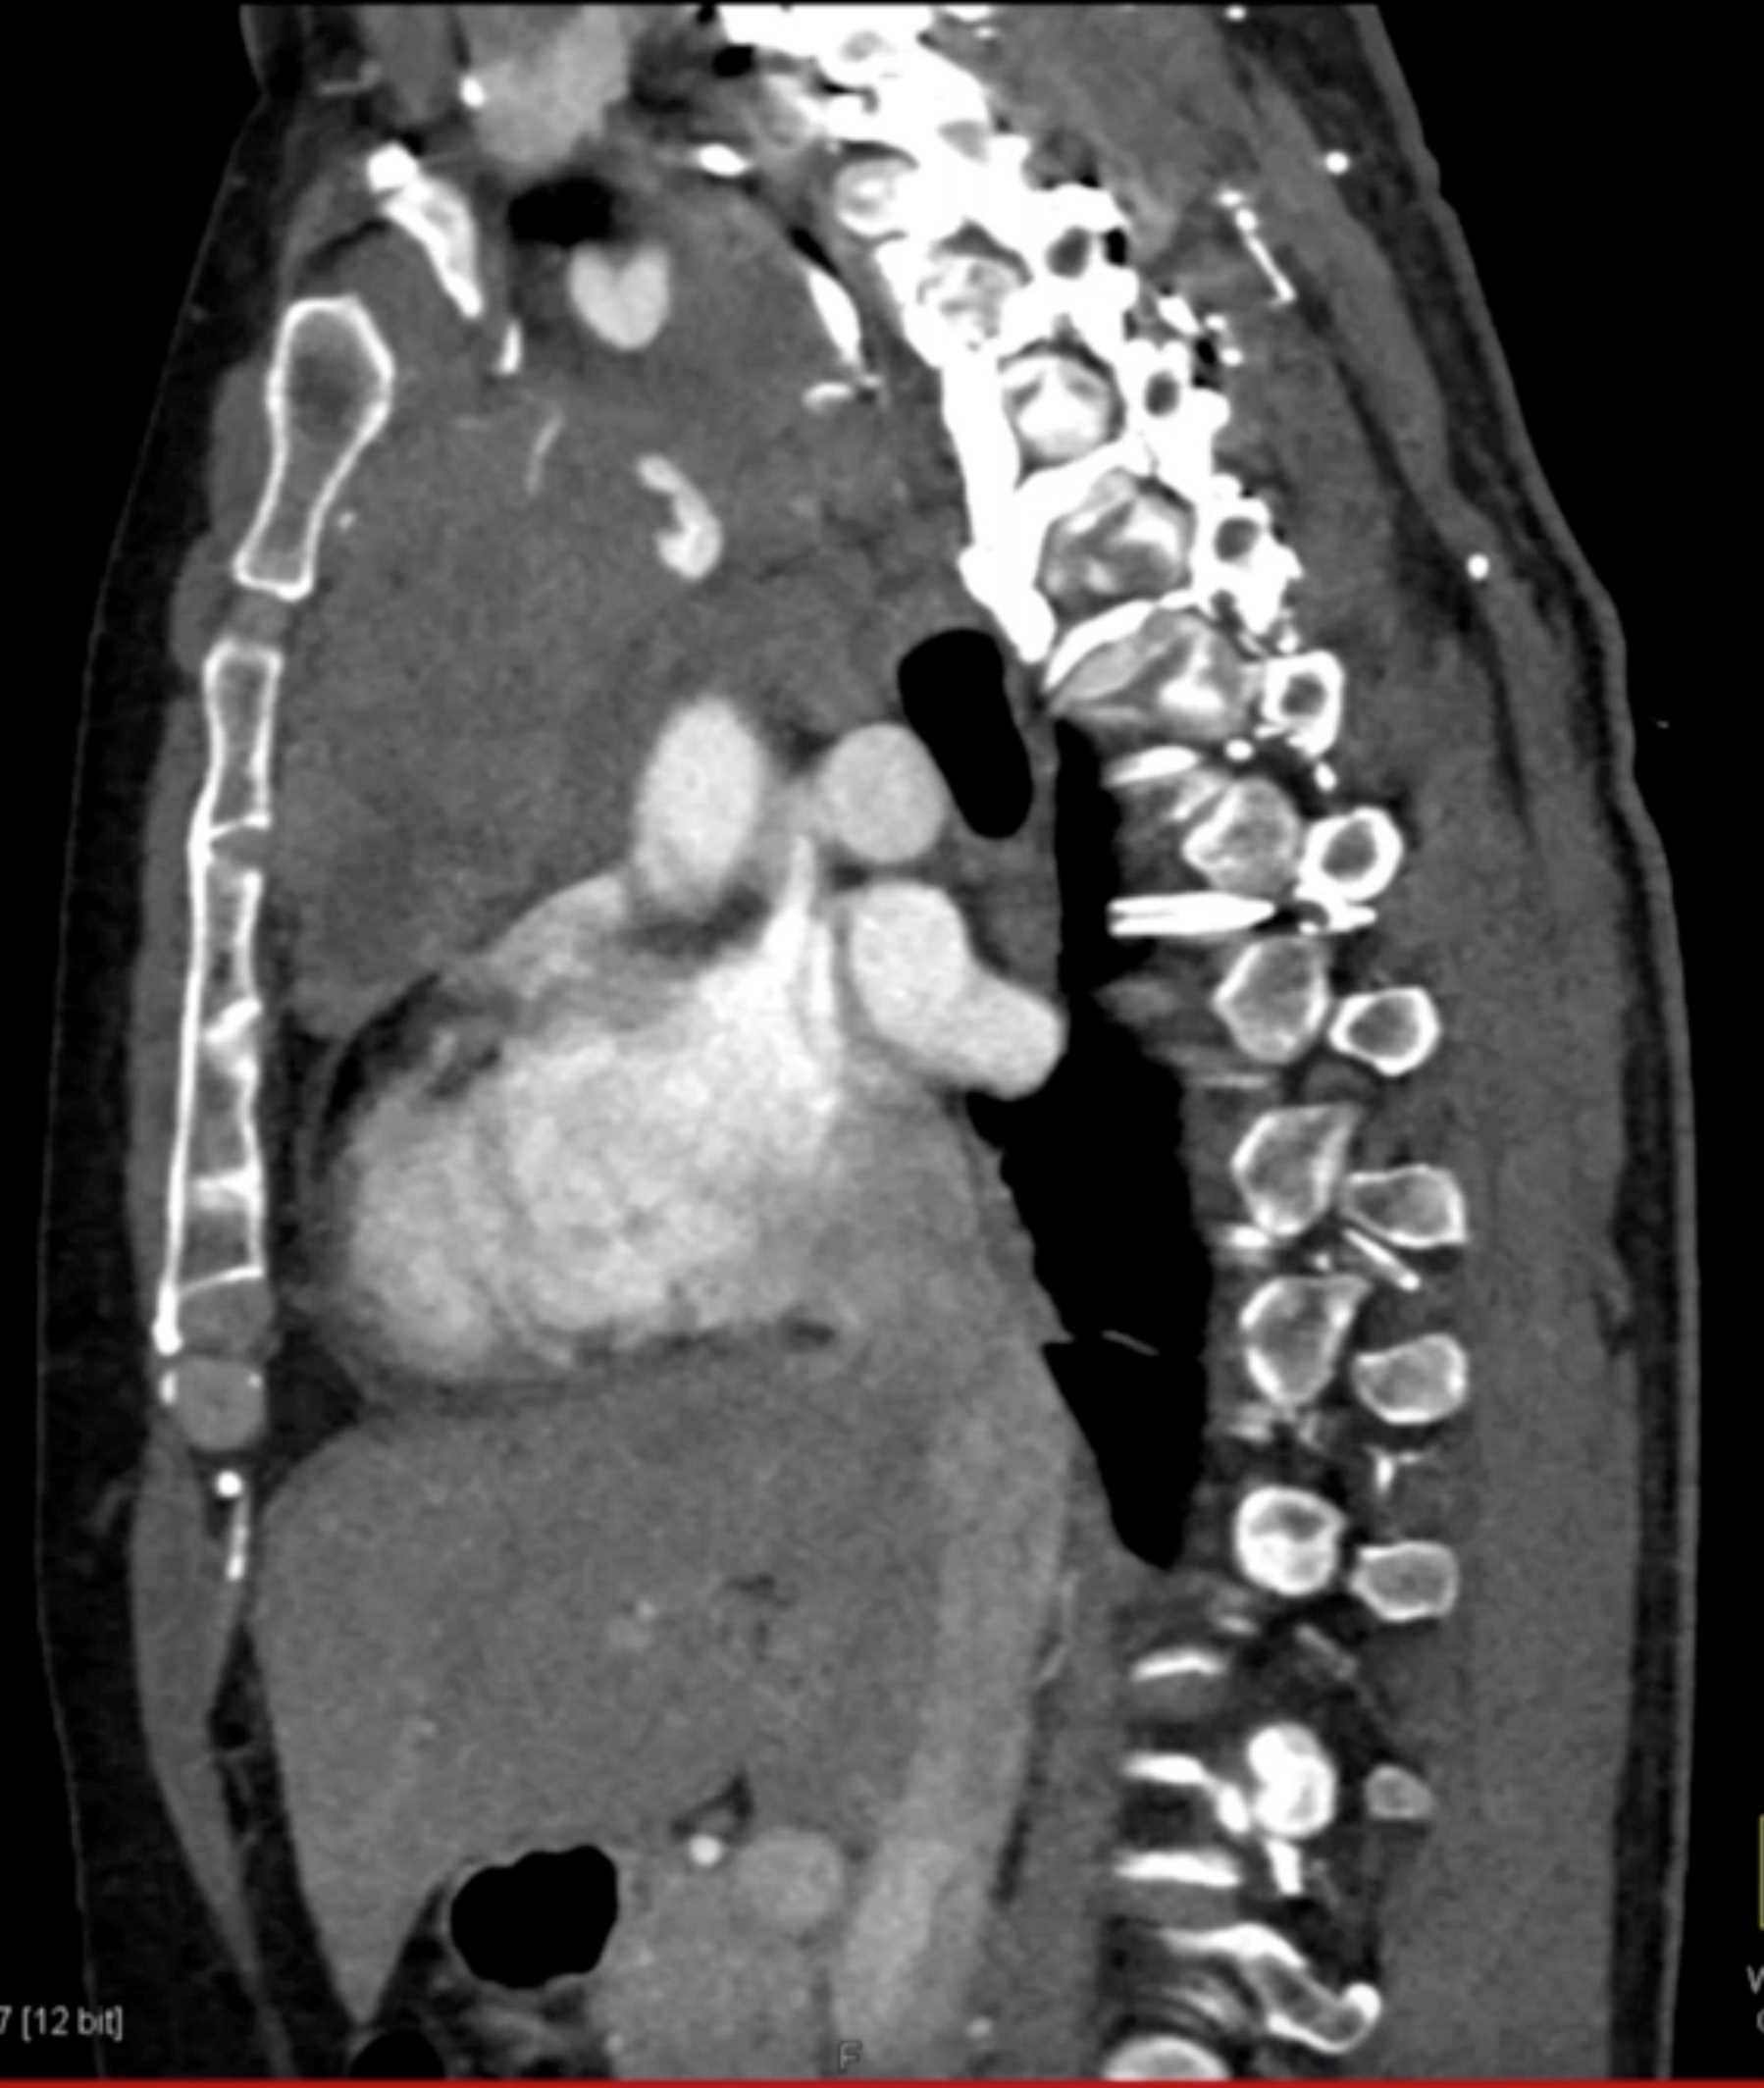

Thymic Carcinoma